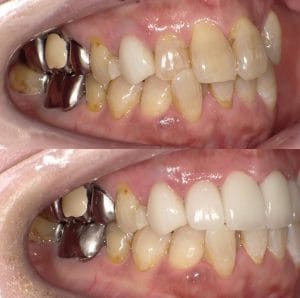

Case022

「歯の長さが短い、歯並びが歪んでる、表面が平面でカッコ悪い、歯茎が腫れている」ということを主訴に来院くださった患者様です。

セラミック矯正は歯科医の技術、センスで仕上がりが全く違うため、審美歯科の中でも担当する歯科医によって最も大きな差の出る診療です。

また、歯並びだけではなく顔貌(お顔立ち)まで綺麗にすることができる診療です。

歯茎の腫れは綺麗に歯を削り直して、正確に型を取り、

精密に作られたセラミックを適合よくセットしてあげることで、前医で入れてから1年以上腫れ続けてた歯茎が1週間で綺麗なピンク色に治りました。

形や並びに関しても、まず歯科医師が「どのような形にするか、どのように並べるか」をイメージしながら綺麗に削ることから始まります。

患者様の主訴通りに綺麗にできて喜んでいただきました。

当院では、患者様の主訴と、治療にかけられる費用、期間によって、ワイヤー矯正、インビザライン、インビザラインGo、セラミック矯正の中から治療法の特徴などをお話しし、その患者様に最適な治療を提案させて頂いております。